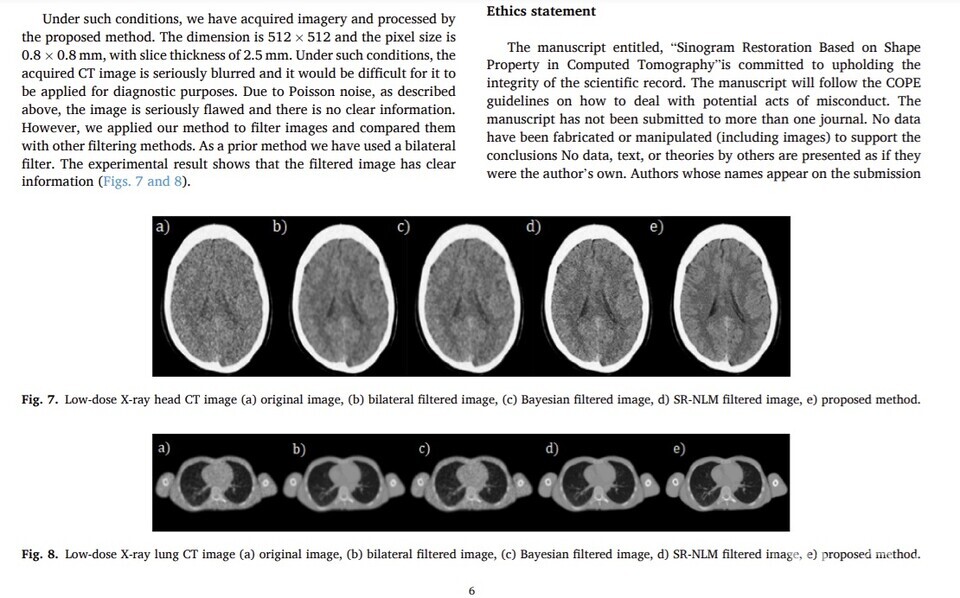

논문은 방사선 노출 위험을 줄이기 위해 얻은 저선량 컴퓨터단층촬영(CT) 이미지 시퀀스가 양자 노이즈와 기타 기계적, 전기적 영향으로 인해 심각하게 저하될 수 있다고 지적했다. 이 문제를 극복하기 위해 먼저 순차적 2차 프로그램(SQP)과 내부 점법(IPM)을 포함한 비선형 최적화 프로그램(NLP)에 기반한 사이노그램 복원 알고리즘을 제시한다는 것이다. 사이노그램은 여러 각도로 X선 사진을 찍어 얻은 그래프를 시각화한 것이다.

논문은 제안된 방법의 효과와 실용성이 디지털 팬텀과 실제 임상 데이터 실험을 통해 검증됐다고 밝혔다.

북한 연구진은 자신들이 필요한 세부 사항을 유지하면서 재구성된 이미지에서 노이즈의 강도를 효과적으로 제거했다고 주장했다. 또 제안된 알고리즘이 기존 알고리즘보다 성능이 우수하다는 것이 정량적 평가와 시각적 측면을 통해 확인됐다고 밝혔다.